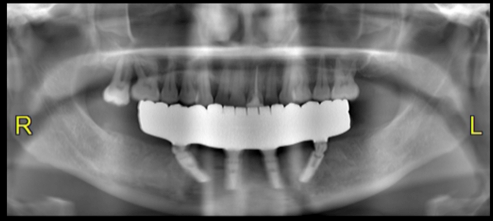

Figure 9 and Figure 10 demonstrate the technology that the dentist and dental laboratory can accomplish within one appointment after diagnostic evaluations, virtual setups, and engineering for provisionals and final restorations. For this patient, occlusion was developed in the laboratory and delivered on surgery day (Figure 11). After 4 months of postoperative healing (Figure 12), the gingival tissues displayed keratinized tissue around the multi-unit abutments. The positive soft-tissue response was consistent with osseointegration of the dental implants. The final restoration was verified with digital scans and analog impressions of the PMMA provisional to replicate the soft-tissue architecture and occlusion related to the opposing arch. A computer-aided and milled zirconia screw-retained full-arch mandibular restoration was implemented, characterized to meet the patient's and dentist's expectations (Figure 13). After screw retention and occlusal verification, a CBCT image was taken to verify final seating of the restoration and radiographic evaluation of the implants (Figure 14).

Fig 14. Panoramic

CBCT image.

Figure 14